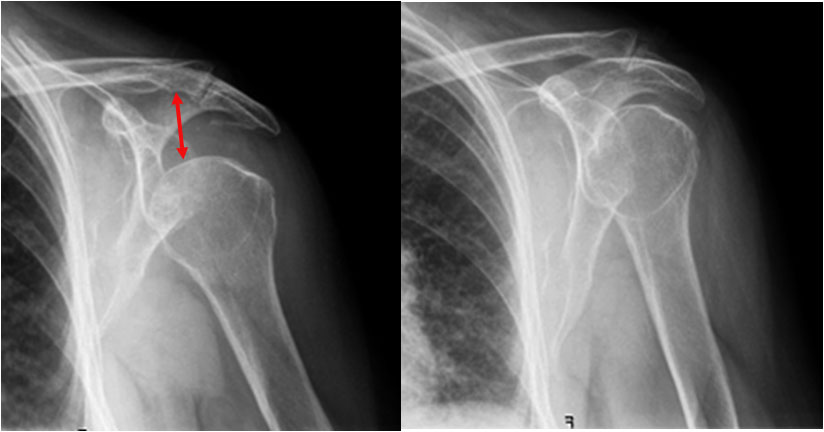

SIGNO DEL HOMBRO CAÍDO

HOMBRO CAIDP

Signo de subluxación inferior de la cabeza humeral, asociada a menudo a fractura, visible en la radiografía anteroposterior del hombro. La cabeza humeral está descendida, pero no existe luxación anterior o posterior del hombro. Suele asociarse a fractura del cuello humeral y es debida a hemartros o lesión músculo-ligamentosa asociada. También existen causas no traumáticas de hombro caído, como la hemiplejia o el compromiso del plexo braquial por un tumor.

La imagen muestra el signo en una luxación humeral (a la izquierda -flecha-) y una radiografía normal del hombro en la que se ve la posición de la cabeza humeral y su relación con la superficie articular eacapular y con la clavícula (a la derecha).